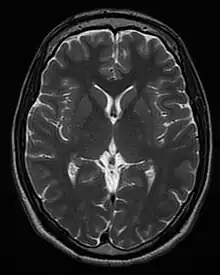

Magnetic resonance imaging (MRI) is a medical imaging technique used in radiology to generate pictures of the anatomy and the physiological processes inside the body. MRI scanners use strong magnetic fields, magnetic field gradients, and radio waves to form images of the organs in the body. MRI does not involve X-rays or the use of ionizing radiation, which distinguishes it from computed tomography (CT) and positron emission tomography (PET) scans. MRI is a medical application of nuclear magnetic resonance (NMR) which can also be used for imaging in other NMR applications, such as NMR spectroscopy.[1]

MRI is widely used in hospitals and clinics for medical diagnosis, staging and follow-up of disease. Compared to CT, MRI provides better contrast in images of soft tissues, e.g. in the brain or abdomen. However, it may be perceived as less comfortable by patients, due to the usually longer and louder measurements with the subject in a long, confining tube, although "open" MRI designs mostly relieve this. Additionally, implants and other non-removable metal in the body can pose a risk and may exclude some patients from undergoing an MRI examination safely.

Neuroimaging

MRI is the investigative tool of choice for neurological cancers over CT, as it offers better visualization of the posterior cranial fossa, containing the brainstem and the cerebellum. The contrast provided between grey and white matter makes MRI the best choice for many conditions of the central nervous system, including demyelinating diseases, dementia, cerebrovascular disease, infectious diseases, Alzheimer's disease and epilepsy.[31][32][33] Since many images are taken milliseconds apart, it shows how the brain responds to different stimuli, enabling researchers to study both the functional and structural brain abnormalities in psychological disorders.[34] MRI also is used in guided stereotactic surgery and radiosurgery for treatment of intracranial tumors, arteriovenous malformations, and other surgically treatable conditions using a device known as the N-localizer.[35][36][37] New tools that implement artificial intelligence in healthcare have demonstrated higher image quality and morphometric analysis in neuroimaging with the application of a denoising system.[38]